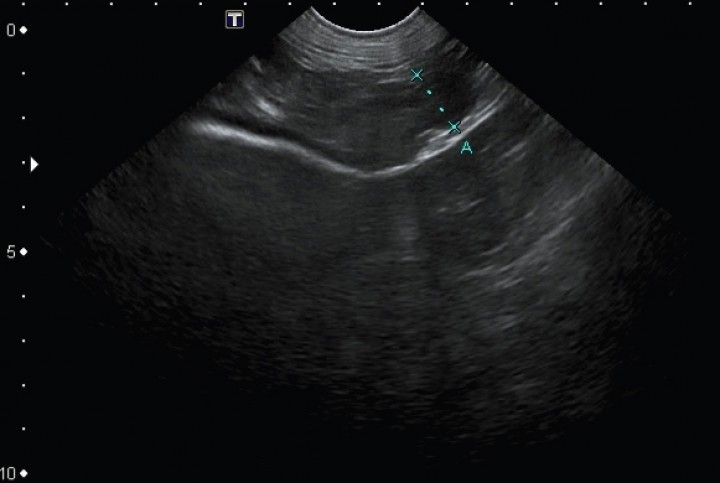

Remiten al servicio de cirugía un Bóxer hembra de 10 años, esterilizada, para evaluación y tratamiento de una masa vascularizada y encapsulada de 2,23cm x 4,74cm, caudal al riñón izquierdo, diagnosticada por ecografía abdominal en su veterinario remitente (Fig. 1).

<p>Imagen ecográfica en la que observamos la masa encapsulada hipoecogénica de 2,23 x 4,74 cm.</p>

Imagen ecográfica en la que observamos la masa encapsulada hipoecogénica de 2,23 x 4,74 cm.